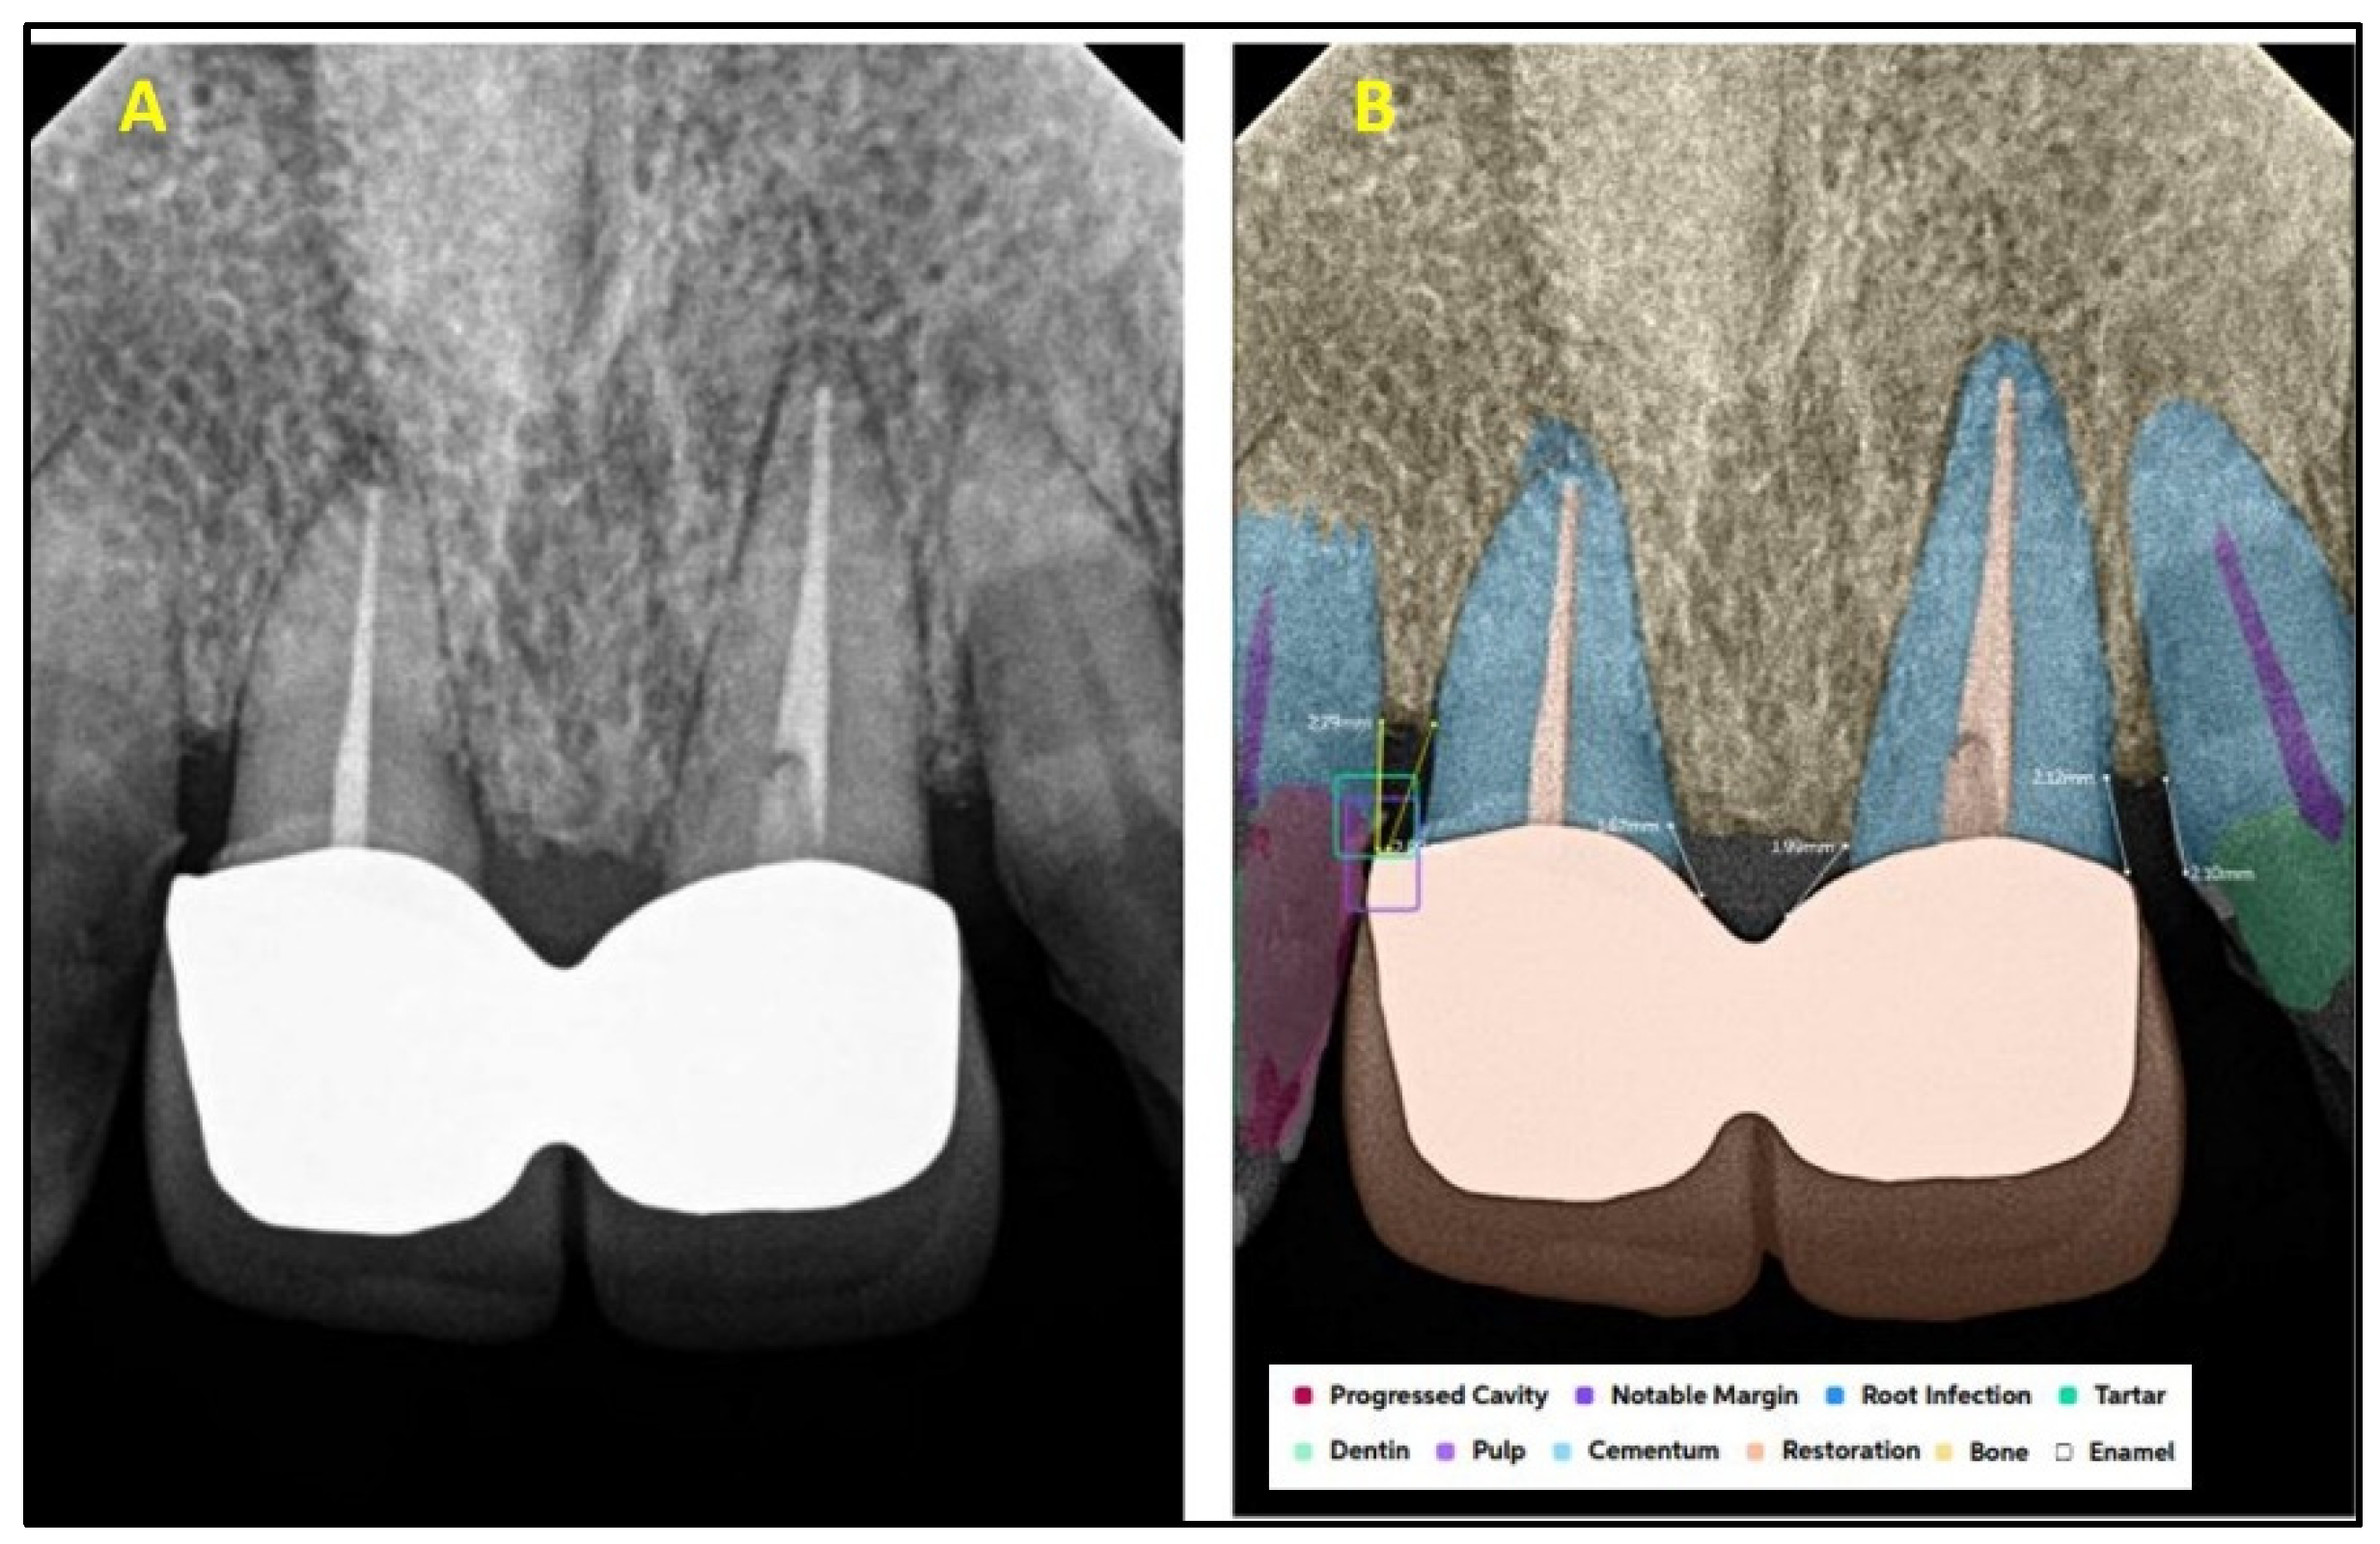

2.2. AI Software Architecture